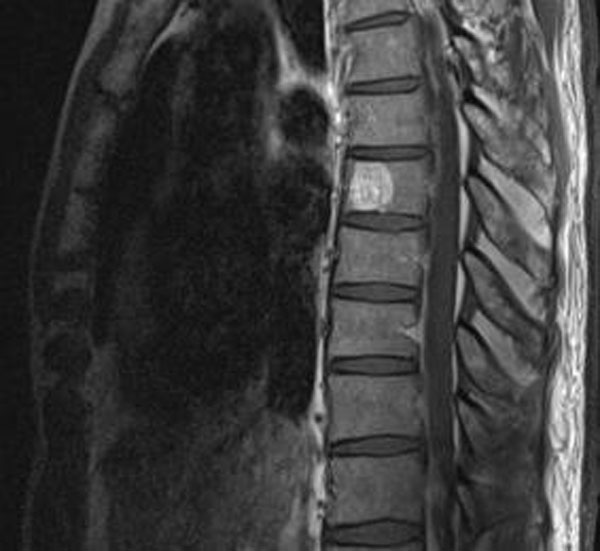

Что можно увидеть на снимках:

- Межпозвонковые диски. МРТ предоставляет четкое изображение межпозвоночных дисков, что делает методику популярной для выявления протрузий, грыж и дисцита (воспалительного заболевания межпозвонковых дисков).

- Кости. МРТ позволяет детально рассмотреть позвонки грудного отдела, их тела и отростки. С помощью этого метода можно выявить инфекционные поражения, нарушения целостности костных структур и изменения после хирургического вмешательства.

- Мягкие ткани. МРТ дает возможность четко оценить состояние мышечных волокон и других тканей, окружающих средний отдел позвоночника. Это исследование помогает обнаружить новообразования, скопления жидкости и инфекционные заболевания.

- Канал позвоночника. На МРТ-снимках хорошо видны стенозы, которые могут вызывать сильные боли и мышечную слабость в спине, грудной клетке или руках.

МРТ грудного отдела позвоночника может выявить различные заболевания, включая межпозвоночные грыжи, остеохондроз, спинальные стенозы, опухоли, воспалительные процессы (например, спондилит), травмы позвонков и дисков, а также патологии мягких тканей и нервных корешков. Этот метод исследования позволяет получить детализированные изображения, что помогает в диагностике и планировании лечения.